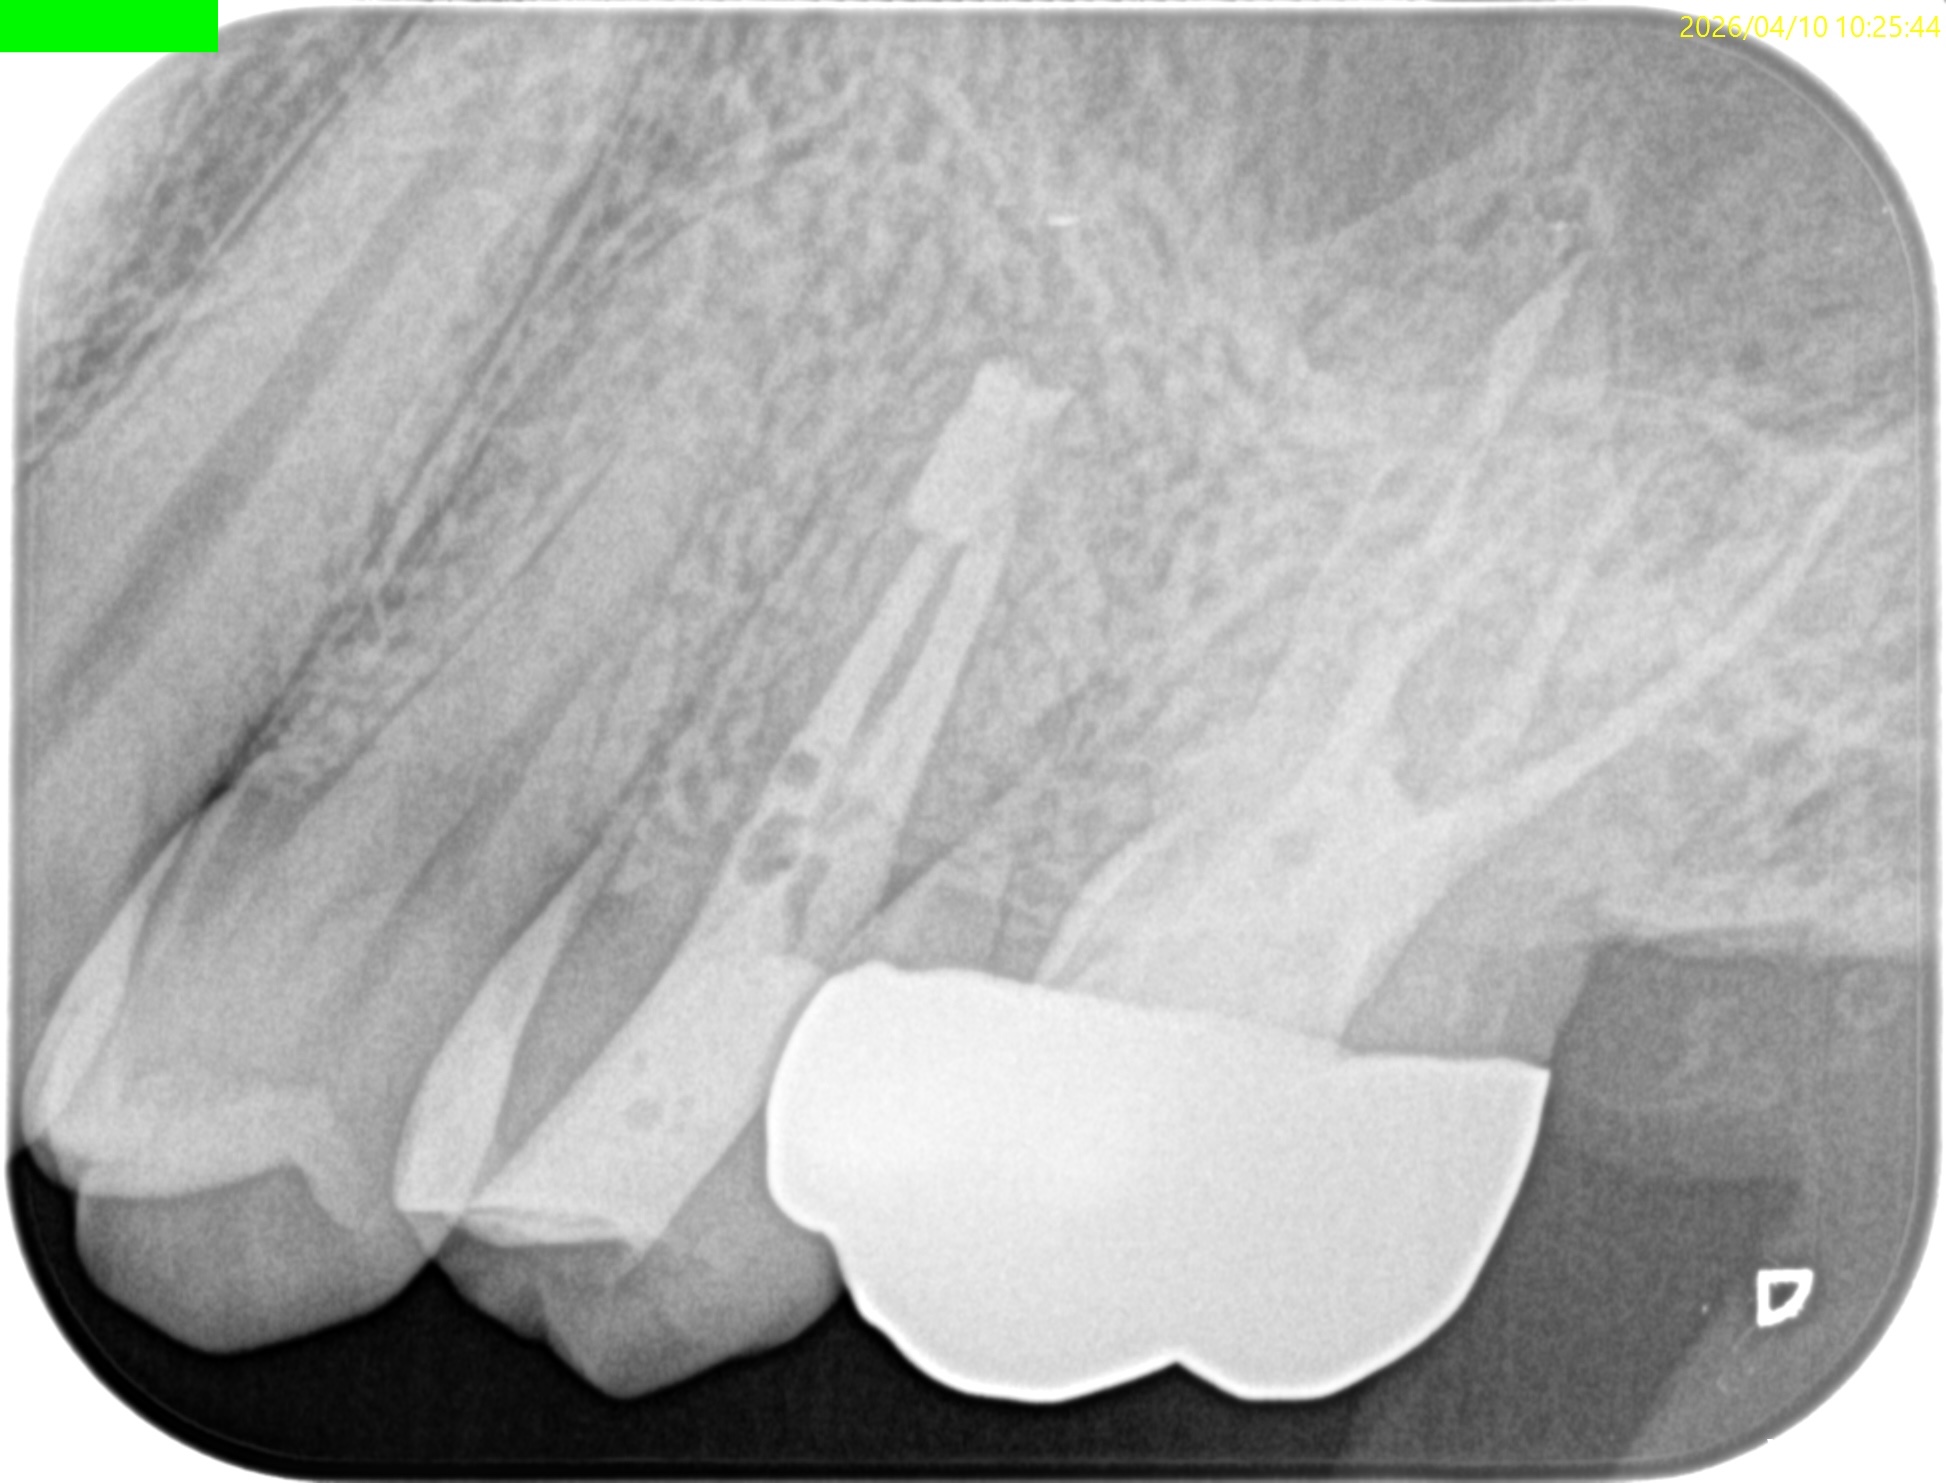

#13 Intentional Replantation 1yr recall(2026.4.10)

1年前と比較した。

歯槽骨の欠損部分は完治した。

打診時のアンキローシス音もない。

ということで、臨床症状もないのでこの日で終診とさせていただいた。